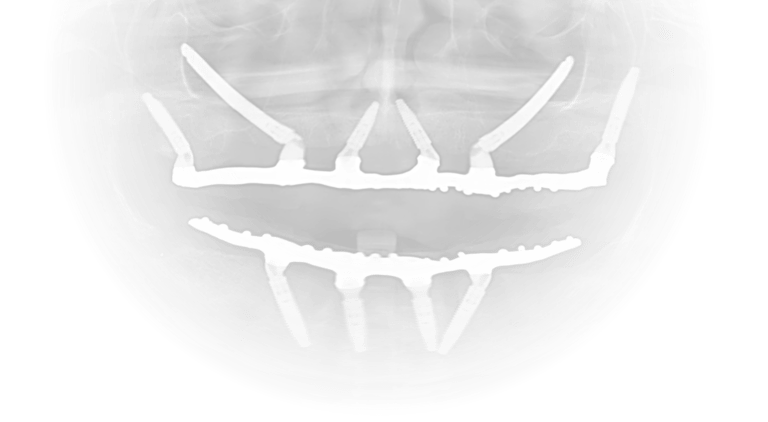

A ZYGO atua em parceria com dentistas que necessitam de suporte em casos de maxilas atróficas e reabilitações complexas. Com a expertise do Dr. Caio Miranda e do Dr. Felipe Antunes, nossa clínica realiza procedimentos de alta complexidade, como implantes zigomáticos com carga imediata, garantindo:

Previsibilidade e planejamento cuidadoso.

Segurança cirúrgica e pós-operatória.

Qualidade clínica e estética nos resultados.